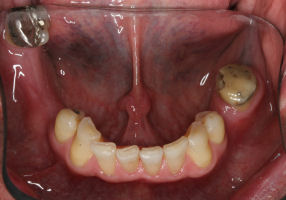

This is an advanced set of dental procedures best carried out by prosthodontists or restorative dentists. Full mouth rehabilitation is a term used in dentistry for rebuilding teeth and supporting structures after decay and gum disease has been stabilised. Full mouth rehabilitation is only required if your bite has collapsed or you have multiple missing or heavily filled teeth. Implants, crown and bridgework and/or partial or full dentures can be used to restore your bite close to its original height. Temporary restorations or dentures are used to get an idea of what the final result will be like before having the final restorations made. Temporary restorations also allow you to have input into your appearance and smile giving you the opportunity to show friends and family what your teeth may look like when the work is complete.

Before/After